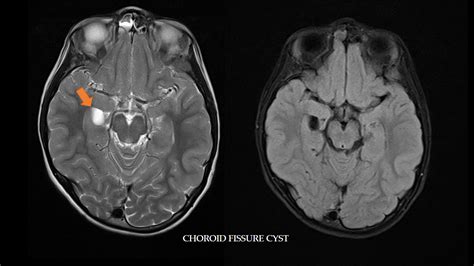

Quiste De La Cisura Coroidea Tratamiento, , , , , , , 0, PPT - PSEUDOLESIONES EN NEUROIMAGEN PowerPoint Presentation, free, www.slideserve.com, 1024 x 768, jpeg, WebThey are usually small and range around about 1-2 cm in diameter. Occasionally, larger cysts may be seen. The cysts are usually round on axial and coronal images, with a characteristic spindle or ovoid shape paralleling the long axis of the. WebQuiste de la cisura coroidea: Se trata de lesiones nodulares bien definidas con localización típica en la cisura coroidea (entre la fimbria del hipocampo y el diencéfalo). Webquiste_de_la_cisura_coroidea. Quiste ovoideo con bordes finos y que por su morfología y localización parecen originarse en la cisura coroidea (espacio entre la fimbria del. WebMe dieron el resultado de una resonancia magnética craneal, todo salió normal a excepción de dos quistes: Pequeño quiste de la cisura coroidea izquierda de 5,8 mm y quiste., 20, quiste-de-la-cisura-coroidea-tratamiento, Novedades y Muebles WebThey are usually small and range around about 1-2 cm in diameter. Occasionally, larger cysts may be seen. The cysts are usually round on axial and coronal images, with a characteristic spindle or ovoid shape paralleling the long axis of the. WebQuiste de la cisura coroidea: Se trata de lesiones nodulares bien definidas con localización típica en la cisura coroidea (entre la fimbria del hipocampo y el diencéfalo). Webquiste_de_la_cisura_coroidea. Quiste ovoideo con bordes finos y que por su morfología y localización parecen originarse en la cisura coroidea (espacio entre la fimbria del. WebMe dieron el resultado de una resonancia magnética craneal, todo salió normal a excepción de dos quistes: Pequeño quiste de la cisura coroidea izquierda de 5,8 mm y quiste.

WebQuiste Fisura Coroidea. Lo primero es definir lo que es la fisura coroidea. Corresponde a un espacio de LCR entre la fimbria del hipocampo y el diencéfalo. Generalmente. WebCisura coroidea. Espacio entre la fimbriadel hipocampoy el diencéfalo. ver quiste de la cisura coroidea. cisura_coroidea.txt. Última modificación: 2019/09/26. Web-Grupo tratamiento: Pacientes con glaucoma tratados durante más de 1 año con al menos 1 antiglaucomatosos por vía tópica. -Grupo control: Pacientes que no reciben ningún. WebQuiste cisura coroidea como hallazgo en TAC solicitado por cefalea. Descargar caso en PDF. Enviar caso a un amigo. Hombre | 42 años. Diagnóstico final: Quiste Cisura. WebAunque mejoran sin tratamiento, es posible eliminarlos con mayor rapidez a través de una inyección de corticoide local o cirugía. Los quistes epidermoides. WebEn caso de que surjan síntomas, se puede intentar controlarlos con medicamentos analgésicos, anticonvulsivos o para el mareo y las náuseas, prescritos. Web6) Quiste de la cisura (fisura) coroidea. La fisura coroidea es una estrecha hendidura de LCR entre el diencéfalo y la fimbria del hipocampo, conteniendo plexos coroideos.. WebA continuación, puedes ver ver un listado de opiniones sobre quiste cisura coroidea y opinar sobre este tema. Aquí podrás encontrar opiniones relacionadas con quiste cisura.

WebQuiste de la cisura (fisura) coroidea. La fisura coroidea es una estrecha hendidura de LCR entre el diencéfalo y la fimbria del hipocampo, conteniendo plexos coroideos. 19,20,21. WebLa mayoria de los quistes son extirpables. Debe consultarlo con un neurocirujano. Para determinar si el quiste es causal de una convulsion deben realizarle EEG y determinar. WebTratamiento: En los casos sintomáticos o lesiones que han alcanzado cierto tamaño, el tratamiento de elección será la resección quirúrgica. Esta puede realizarse por medio de.

Web6) Quiste de la cisura (fisura) coroidea. La fisura coroidea es una estrecha hendidura de LCR entre el diencéfalo y la fimbria del hipocampo, conteniendo plexos coroideos.. WebA continuación, puedes ver ver un listado de opiniones sobre quiste cisura coroidea y opinar sobre este tema. Aquí podrás encontrar opiniones relacionadas con quiste cisura. Web• Quiste de los plexos coroideos • Quiste de la cisura coroidea • Quistes aracnoideos (2%) • Quistes de la pineal (2 – 4%) • Lipoma del filum terminale • Quistes perineurales de.